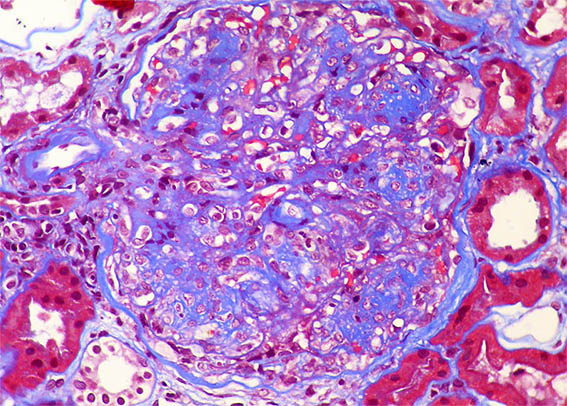

Figure 3. Masson's trichrome stain, X400.